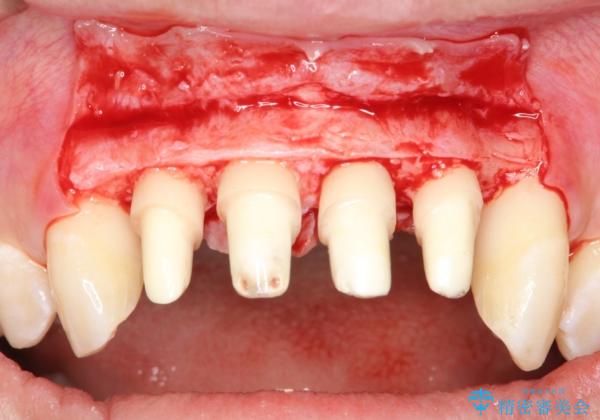

侵襲性歯周炎。前歯の歯周補綴

- 前歯がグラグラすることを主訴に来院されました。

再生治療後、歯周補綴を行っております。

歯周病が進行してしまった歯に対し、再生治療および歯周補綴を行うことで歯周組織の安定を得ることができました。